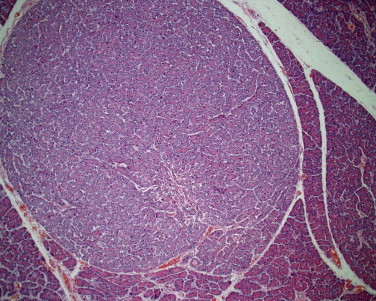

Figure 29-2.

Persistent shallow gastric ulceration, with flattening and basophilia of the surface epithelium combined with loss of the foveolar mucus neck cells in favor of an expanding population of hyperchromatic germinal cells. As is typical for chemical or mechanical gastric ulceration, there is very little recruitment of leukocytes.

Canine fundic stomach with glandular atrophy, glandular nesting, and lamina propria in the absence of any significant infiltration of leukocytes. This is a common lesion, but with no proof that it is medically significant.